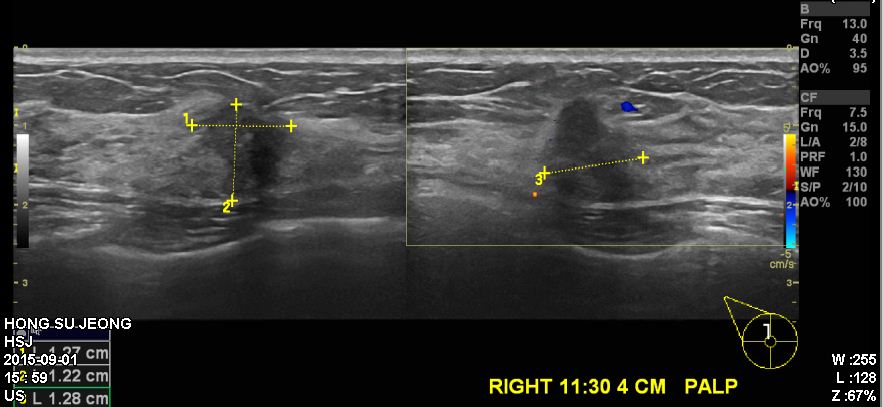

검진상 이상소견으로 내원하신 40 여성분으로 우측 유방 11시 30분 방향에서 4cm 떨어진

곳의 만져지는 혹 본원에서 조직검사 시행 하였으며 우측 침윤성 유관암 진단 되었습니다.